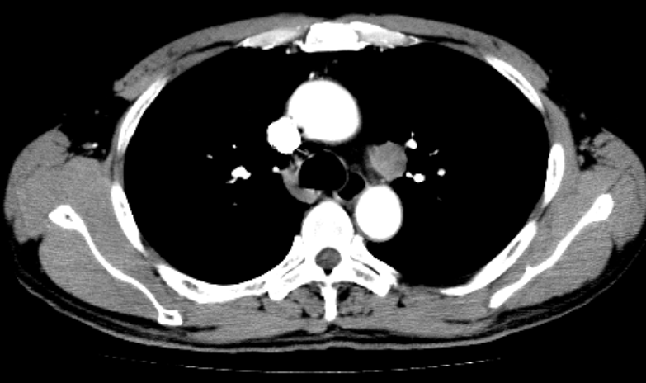

2016.12:双肺门及纵隔未见明显肿大淋巴结

2017.5:主-肺动脉窗新增一肿大淋巴结,大小约19mm×23mm